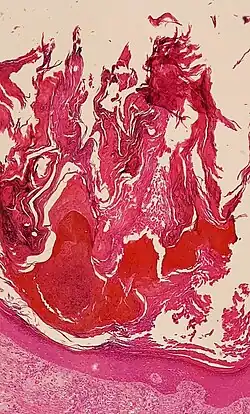

El estrato córneo es el tejido muerto que realiza funciones fisiológicas, protectoras y adaptativas que incluyen cizallamiento mecánico, resistencia al impacto, flujo de agua y regulación de la hidratación, proliferación microbiana y regulación de la invasión, inicio de la inflamación a través de la activación de citocinas y la actividad de las células dendríticas, y permeabilidad selectiva para excluir toxinas., irritantes y alérgenos.[5] Esta capa se compone de 15 a 20 capas de células aplanadas sin núcleos ni orgánulos celulares. Su citoplasma muestra queratina filamentosa. Estos corneocitos están incrustados en una matriz lipídica compuesta de ceramidas, colesterol y ácidos grasos.[6]

El grosor de la capa córnea varía en todo el cuerpo. En las palmas de las manos y las plantas de los pies (a veces rodillas, codos,[9] nudillos) esta capa es estabilizada y construida por el estrato lúcido (fase clara) que permite que las células concentren la queratina y las endurezcan antes de que se elevan a un estrato córneo típicamente más grueso y más cohesivo. El estrés mecánico de la fuerte tensión estructural provoca esta fase stratum lucidum en estas regiones que requieren protección adicional para agarrar objetos, resistir la abrasión o el impacto y evitar lesiones. En general, la capa córnea contiene de 15 a 20 capas de corneocitos y cuenta con un espesor entre 10 y 40 μm.

La hiperqueratosis es un aumento del grosor del estrato córneo y es un hallazgo inespecífico que se observa en muchas afecciones de la piel.